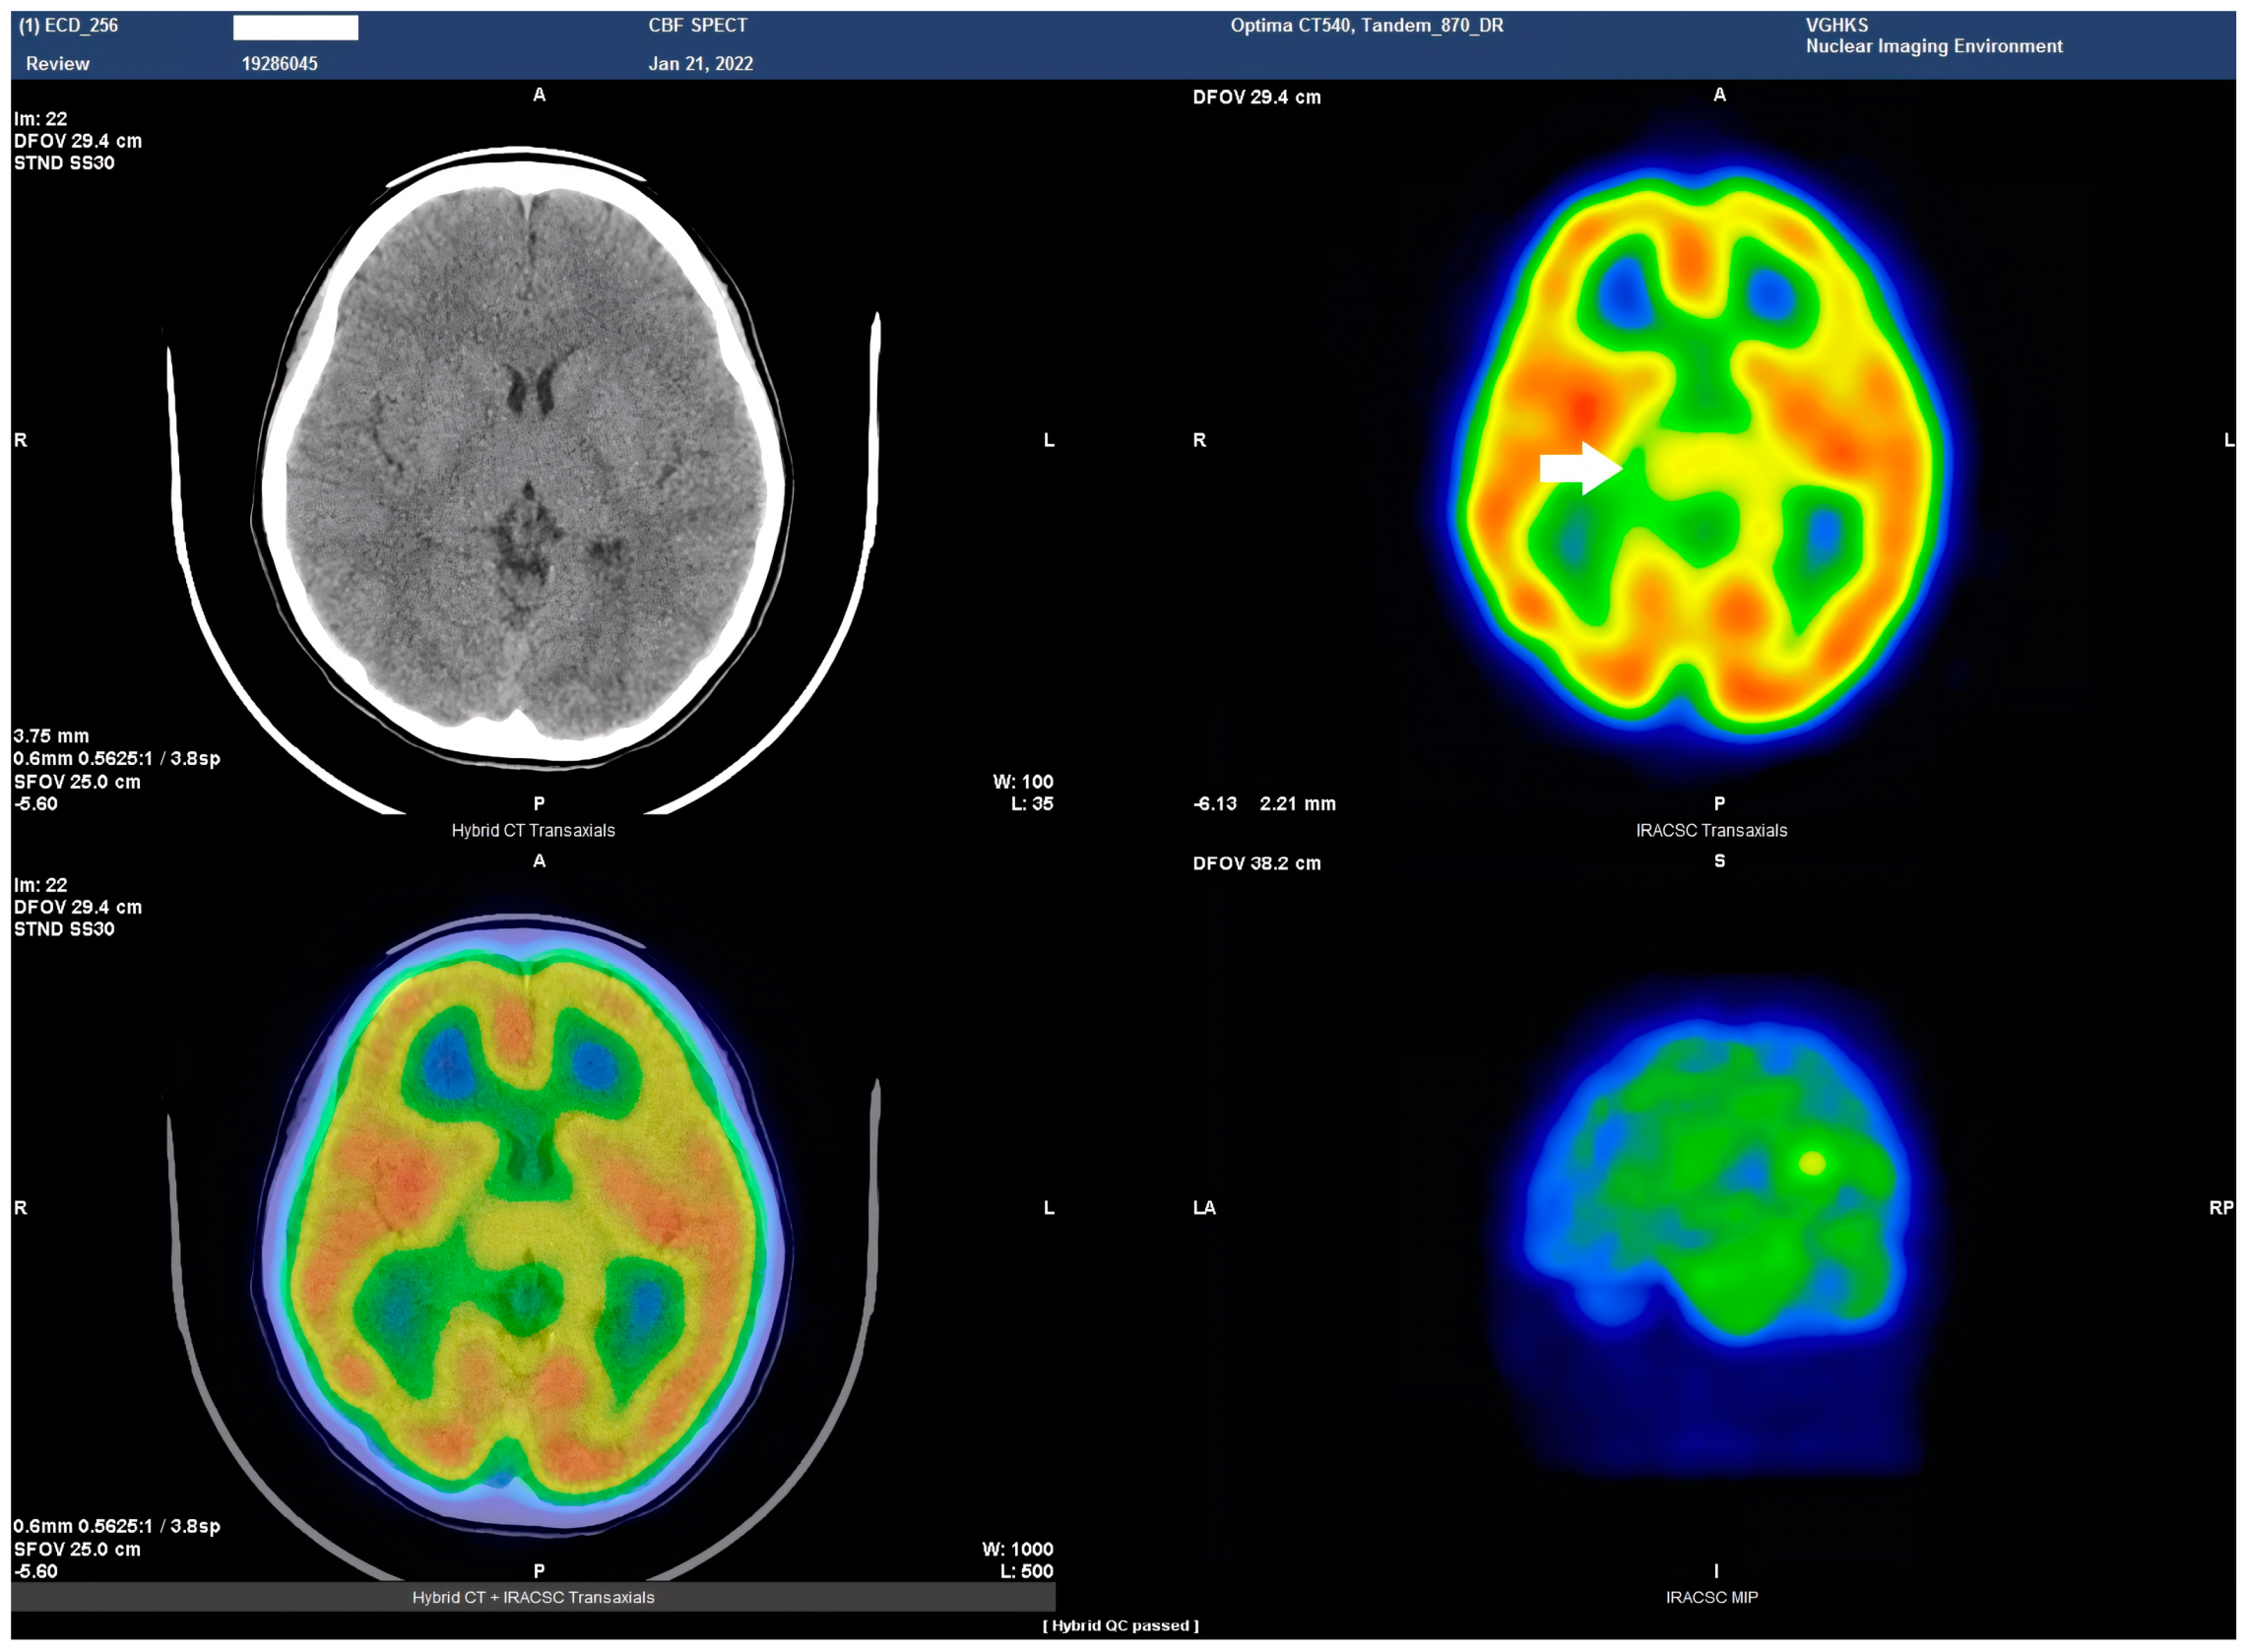

Figure 3. Axial view of the Tc−99m ECD brain perfusion SPECT study. A decreased uptake in the tracer can be observed in the thalamus (arrow). Left upper panel, CT image; right upper panel, SPECT; left lower panel, the combined SPECT and CT images.